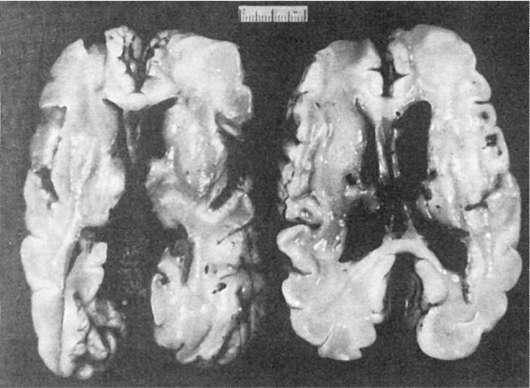

незрелости их сосудистого русла. Являются источником внутрижелудочковых кровоизлияний с возможной последующей тампонадой их полостей (рис. 310).

Рис.

310. Тампонада желудочков мозга при внутрижелудочковых кровоизлияниях у недоношенного новорожденного

Внутрижелудочковые кровоизлияния могут распространяться на все желудочки мозга с тампонадой мозжечково-луковичной цистерны и субарахноидальных пространств. Сочетаются с гиалиновыми мембранами в легких новорожденных.

Дают высокий процент летальности.